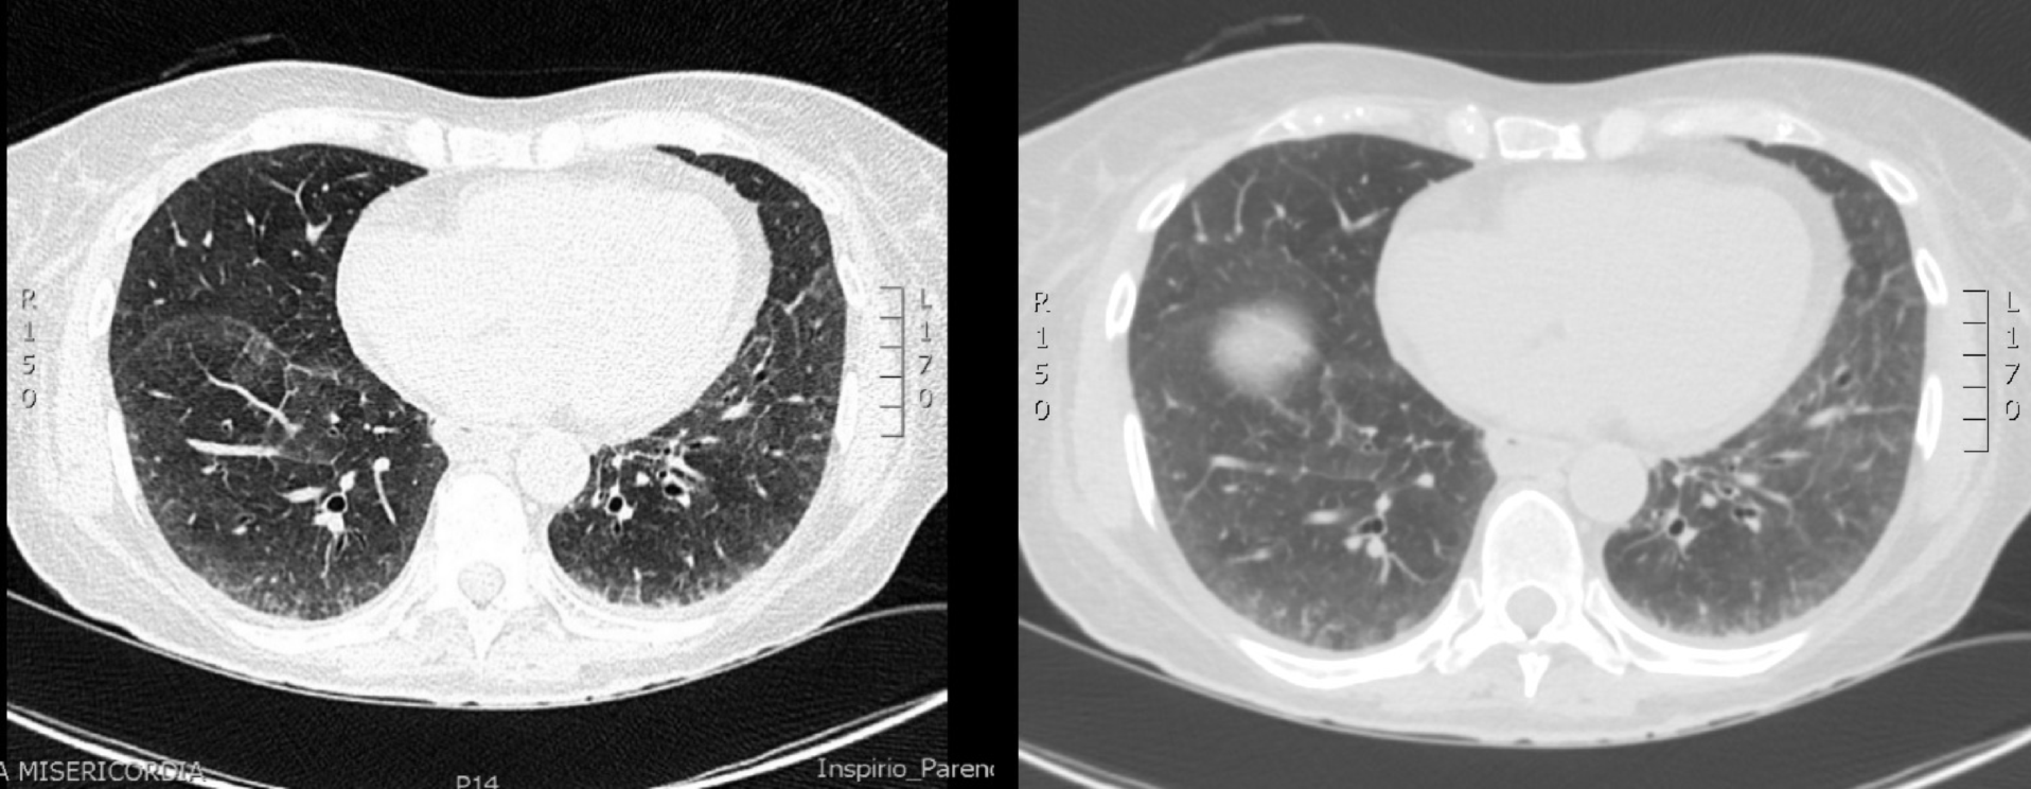

During hospitalisation, the echocardiography showed mild increase in left ventricle (LF) thickness with interventricular septal of 12 mm, not justified by the presence of valvulopathy or systemic arterial hypertension. NT-proBNP was also elevated (1170 pg/ml). Coronary angiography showed no lesions. Serum immunofixation revealed IgM kappa at 6.1 g/L, kappa (κ) light chains at 123 mg/L (normal range: 6–22 mg/L), and lambda (λ) light chains at 53 mg/L (normal range: 5–26 mg/L), with traces of κ light chains on urinary immunofixation. Bone marrow biopsy showed findings consistent with IgM “plasma cell-like” monoclonal gammopathy of undetermined significance (MGUS) without amyloid deposits (Congo red staining and polarized light microscopy were negative). In December 2023, she was admitted again to the cardiology unit due to fatigue, severe dyspnea requiring oxygen supplementation up to 12 L/min, orthostatic hypotension, and elevated troponin levels (1010 ng/L). Echocardiography confirmed mildly increased LV wall thickness with slight of the interventricular septum and preserved EF, with normal filling pressure. High-resolution chest computed tomography (HRCT) showed mosaic attenuation pattern in the middle lobe and lingula, diffuse ground-glass opacities at the bases with interlobular septal thickening and dilated oesophagus (Fig. 1).

Fig. 1

HRCT showing a mosaic attenuation pattern and diffuse ground-glass opacities at the lung bases with interlobular septal thickening

After three months of treatment, the patient reported further improvement in dyspnea and fatigue. Follow-up HRCT showed reduced ground-glass opacities but persistent basal reticular patterns bilaterally (Fig. 3).

Fig. 3

Follow-up HRCT showing a reduction in ground-glass opacities but persistent bilateral basal reticular pattern